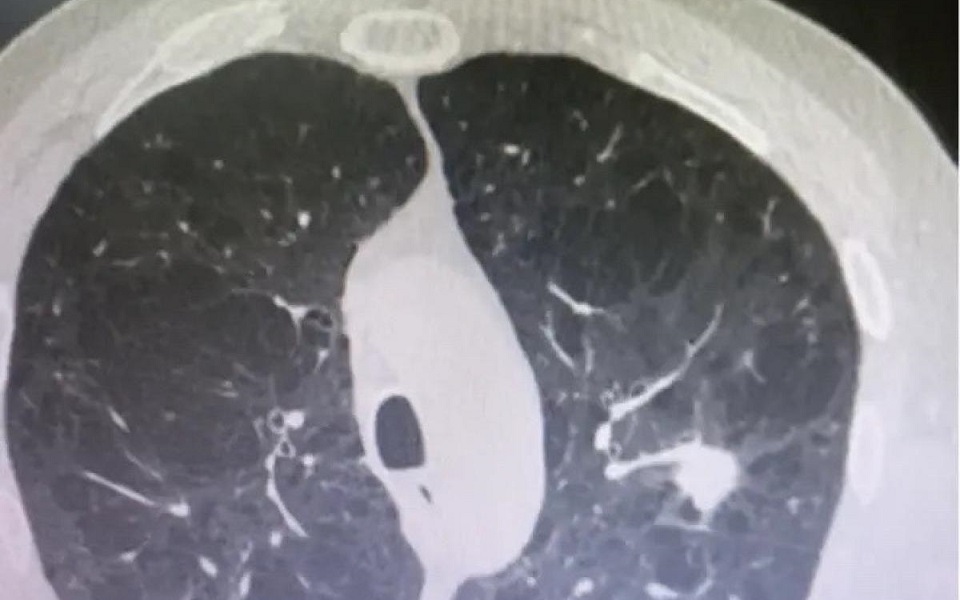

В Рязанском онкологическом диспансере 78-летнему пациенту удалили опухоль, которая вросла в сосуд, и спасли легкое. Об этом сообщили в пресс-службе учреждения.

В лимфатических узлах пенсионера выявили метастазы, проникшие в легочную артерию. Ранее в таких случаях полностью удаляли легкое, что приводило к ограничениям в жизни для пациентов.

Специалисты решили провести операцию по частичному удалению ткани органа вместе с пораженным участком артерии. Этот подход позволил сохранить большую часть функция легкого и обеспечить оптимальные условия для восстановления мужчины.

Иллюстрации:  Рязанский онкодиспансер